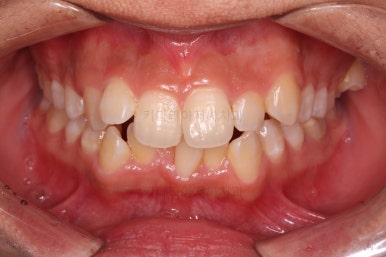

종료 시의 사진들을 전후 비교해 보겠습니다.

입매가 좋아졌고 입을 다무는 편안함도 좋아졌으며 치열이 가지런해졌으며 웃을 때 보이는 치열의 느낌도 좋고 교합도 잘 마무리 되었네요.

지켜봐도 되는 충치는 지켜보기로 여지를 남기고 필요한 충치치료도 마무리를 했습니다.

이상 부산청소년치아교정 키다리아저씨치과에서 시행한 덧니, 돌출입 개선 사례였습니다.